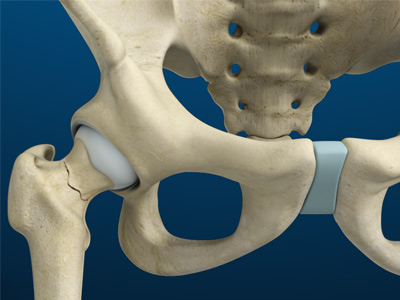

The hip joint is the junction where the hip joins the leg to the trunk of the body. It is comprised of two bones: the thigh bone or femur and the pelvis which is made up of three bones called ilium, ischium, and pubis. The ball of the hip joint is made by the femoral head while the socket is formed by the acetabulum. The Acetabulum is a deep, circular socket formed on the outer edge of the pelvis by the union of three bones: ilium, ischium, and pubis. The lower part of the ilium is attached by the pubis while the ischium is considerably behind the pubis. The stability of the hip is provided by the joint capsule or acetabulum and the muscles and ligaments which surround and support the hip joint.

The head of the femur rotates and glides within the acetabulum. A fibrocartilagenous lining called the labrum is attached to the acetabulum and further increases the depth of the socket.

The femur or thigh bone is one of the longest bones in the human body. The upper part of the thigh bone consists of the femoral head, femoral neck, and greater and lesser trochanters. The head of the femur joins the pelvis (acetabulum) to form the hip joint. Next, to the femoral neck, there are two protrusions known as greater and lesser trochanters which serve as sites of muscle attachment.

Articular cartilage is the thin, tough, flexible, and slippery surface lubricated by synovial fluid that covers the weight-bearing bones of the body. It enables smooth movements of the bones and reduces friction.

- Acetabular labrum: The labrum is a fibrous cartilage ring which lines the acetabular socket. It deepens the cavity, increasing the stability and strength of the hip joint.